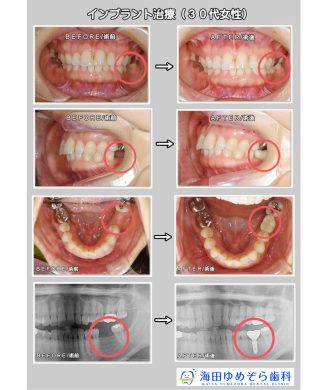

インプラントの症例 GBR法/骨補填材使用

今回はGBRを行ったインプラント治療の症例です。

GBR法とは、インプラント治療において骨が少ない方の場合に、

顎の骨の再生を促して骨の厚みを増やす方法です。